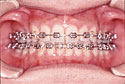

歯列矯正・矯正歯科は、矯正装置を使用して歯に人工的な力を加えることで上顎・下顎の骨の形態に変化を起こし、ふぞろいな歯並びや咬み合わせを整える治療です。

治療前 治療後

おのざき歯科医院では既製のワイヤーなどはほとんど使わず、患者さん一人一人にあったワイヤーを制作して装着する方法をとっています。

おのざき歯科医院の矯正治療は、「きれいに歯が並び・きちんと咬めて・さらに顔も美しく」ということに目標をおいています。